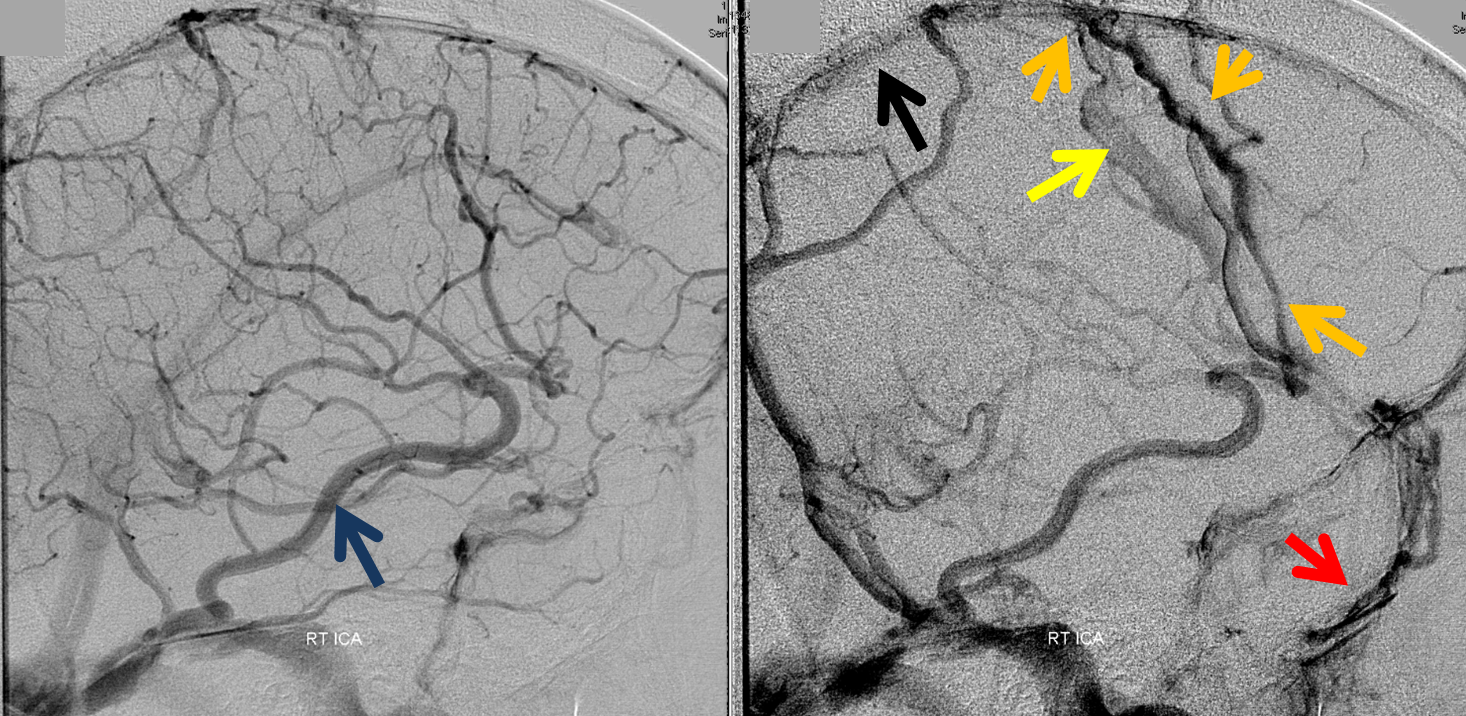

Below is a case of severe venous sinus thrombosis and secondary parenchymal venous infarcts

The explanation for the above tragic pattern is below. On the right, sigmoid and transverse sinuses are patent. However, the Labbe is hypoplastic, and majority of outflow used to go to the Trolard, into the now occluded SSS. There is no other effective way to go — the trolard tries to decompress via a left diploic vein, and convexity tries to access the deep venous system (which normally should not be well-seen in setting of hypoplastic right A1 segment). The left situation is much better, as well-developed superficial sylvian veins drain into the patent Cavernous Sinus. Thus, despite thrombosis of the left transverse and sigmoid sinuses, the left hemisphere is doing better, while the right one, which has patent transverse and sigmoid sinuses, is devastated.

Post venous thrombectomy — with limited results. Note presence of same left diploic vein as seen in right ICA injection, and connection between the distal superior sagittal sinus and the deep venous system via the inferior sagittal sinus.